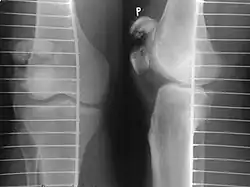

Tension band wiring: front and side view

Most patella fractures are transverse or comminuted, hence the quadriceps mechanism is disrupted and they are treated by a combination of wires in a tension band construct. This unites the fractured bones, reconstructing the straightening mechanism of the leg.[5][6]